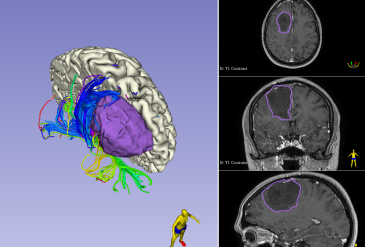

Внутримозговая опухоль правой лобной доли. Удаление астроцитомы G4.

10.07.2025 Пациентка М., 38 лет. Обратилась с жалобами на единственный приступ утраты сознания, сопровождавшийся судорогами. Со слов пациентки, за 2 недели до обращения, утром, после ночного сна, на фоне полного видимого здоровья, развился приступ утраты сознания, сопровождавшийся судорогами. При обследовании, в правой лобной доле выявлено внутримозговое объёмное образование, с эффектом лишнего...